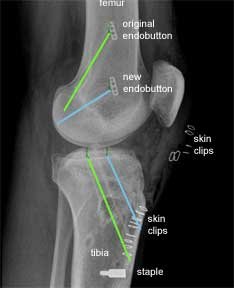

This X-ray is from the front as before. The original endobutton was not removed. If you follow the line of the new femoral tunnel it is clear that it has been drilled from an antero- medial portal as the blue line points to two skin clips at this point.

There are further skin clips indicating an antero-lateral arthroscopic portal and a medial proximal tibial incision made to harvest the hamstring graft and drill the tibial tunnel. The larger white implant at the lower end of the tibia is a staple. This is put in for extra support in revision cases. This is in addition to the PEEK screw which was described earlier.

This is an X-ray, of the same patient, taken from the side instead of the front. The green lines show the original tunnels and the blue lines the new tunnels.

For the femoral tunnels the higher endobutton is from the original procedure and the lower endobutton is from the revision procedure.

The new tibial tunnel (blue) is more anterior (closer to the front) than the original tunnel. This is a more anatomic position for the tibial insertion of the native ACL.